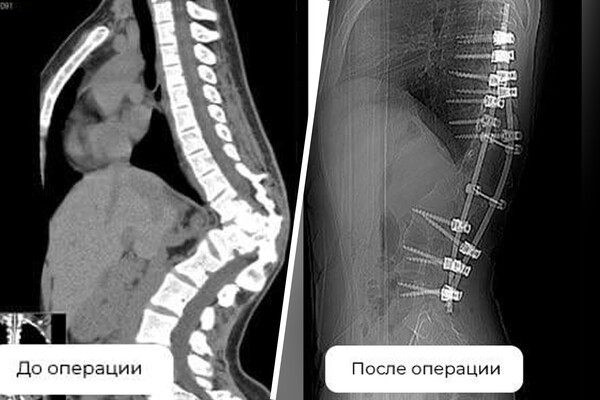

Девушке был диагностирован кифосколиоз — S-образное искривление позвоночника с образованием задней выпуклости в грудном отделе. На фоне врожденной патологии — неправильно сформированного позвонка — у нее развился сколиоз 72 градуса и вырос горб.

Чтобы помочь девушке, медики провели три операции. Во время первой ей установили аппарат внешней фиксации, во время второй — удалили деформированный позвонок в грудном отделе и сделали дополнительную коррекцию. В ходе третьего вмешательства позвоночник пациентки зафиксировали внутренней конструкцией.